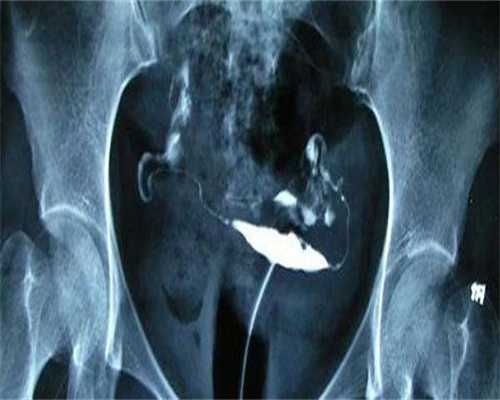

全球试管婴儿总数1、试管婴儿是指从女人的卵巢内取出卵子,然后让卵子和男方精子结合,形成胚胎后就转移胚胎到子宫里,让胚胎在子宫里着床、妊娠的过程。和正常受孕最大的不同就是,试管婴儿是通过人工让精子和卵子合成形成受精卵后在移入子宫内。

2、进行取卵取精,现在取卵在静脉麻醉下进行的,所以不用担心感到穿刺过程的痛苦,也不用担心疼痛。实验室会为做试管婴儿的夫妇培养10个左右的胚胎,这些不能全部移植到妈妈的子宫里,太多会很危险,胚胎的移植还会根据患者的年龄,曾经怀孕与否及胚胎的质量移植2到3个。剩下的胚胎就放在-196摄氏度的液氮罐中保存。

3、体外受精和培养:将采集的卵子根据成熟程度分类后,放到培养液中4-30小时至其完全成熟。18小时后精子和卵子自由结合。

4、胚胎移植:胚胎在培养器皿里生存3天至5天,再移植到女人子宫内,但是如果患者的年龄在35岁以下的话,还是第一次做试管婴儿手术,最多只能植入两个胚胎,超过35岁的患者,最多只能放3个胚胎,剩下的会被冷冻,如果没有成功,再拿出来移植。

5、妊娠确定:在胚胎移植后14天测定血清HCG,了解胚胎发育的情况。30天可经阴道超声检查,确定是否与宫内妊娠,是否有胎心搏动。